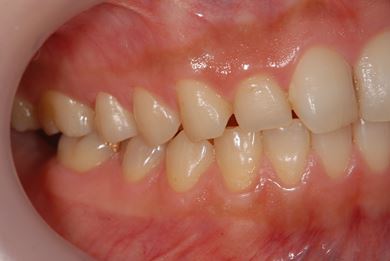

インプラントの症例写真 IMPLANT

インプラント治療+セラミック治療+歯肉歯槽骨整形

| 性別/年齢 | 女性 / 38歳 | ||||||||||||||||||||||||||||||||

| 主訴 | 右下奥の欠損のため、インプラントを希望。また、左に物が挟まりやすいための治療も希望。 | ||||||||||||||||||||||||||||||||

| 治療内容 | インプラント1本、ジルコニアフレームオールセラミッククラウン2本(ジルコニアセラミック用土台1本)、歯肉歯槽骨整形 | ||||||||||||||||||||||||||||||||